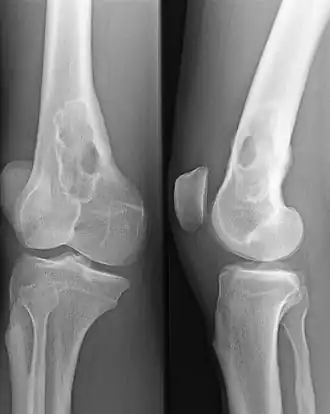

Złamanie patologiczne (łac. fractura pathologica) – złamanie kości zachodzące w wyniku drobnego urazu, a często bez uchwytnego urazu, przy czym struktura tkanki kostnej osłabiona jest w wyniku uogólnionego lub miejscowego procesu chorobowego. Może je wywołać nawet błahy uraz, który w warunkach fizjologicznych nie powoduje uszkodzenia.